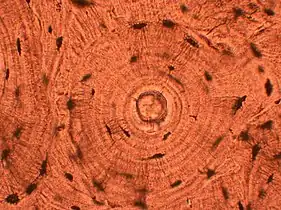

Whorled: Multiple concentric objects, or spiral-shaped

Cartwheel pattern: Center points that radiate cells or connective tissue outward